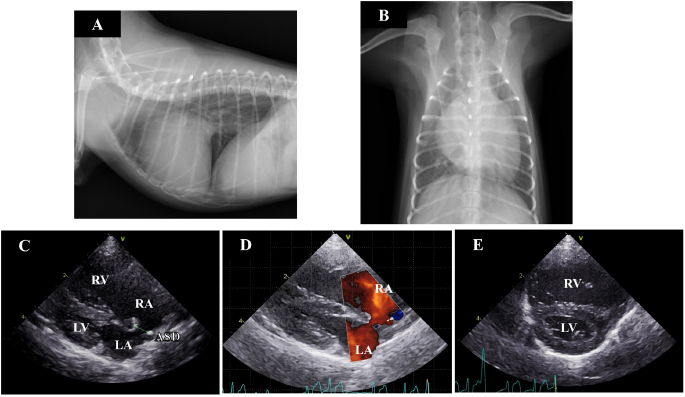

A 7-month-old female toy poodle weighing 1.4 kg was referred to the Okayama University of Science Veterinary Teaching Hospital with cardiac dilatation. The dog was maldeveloped. No cardiac murmur was detectable through thoracic auscultation, and there were no respiratory abnormalities. Complete blood count and serum biochemical test results were within reference ranges. Thoracic radiography revealed a right-sided cardiomegaly, pulmonary overcirculation, and main pulmonary artery enlargement without any tracheal, bronchial, or pulmonary abnormalities or lesions (Fig. 1a and b). Electrocardiography revealed a right-axis deviation (–150°) as well as a deep S-wave (–1.5 mV) and no arrhythmia. Echocardiography evaluation revealed moderate dilatation and concentric hypertrophy of the RV with ventricular septal flattening, enlargement of the right atrium (RA), and main pulmonary artery enlargement (pulmonary artery-to-aorta ratio: 1.34). A secundum-type ASD was also observed, and the blood flows though the defect exhibited a left-to-right shunt (Fig. 1c–e). The size of the defect was 3.3–4.0 mm, and the pulmonary blood flow/systemic blood flow ratio (Qp/Qs) as determined through echocardiography was 3.03. Based on these observations, the isolated secundum-type ASD was diagnosed. Due to the risk of progression of pulmonary hypertension, heart failure, or right-to-left shunt, ASD closure using an Amplatz canine duct occluder was planned.

Fig. 1. Thoracic radiography and echocardiography on the first examination. (a) and (b): Thoracic radiography revealed a right-sided cardiomegaly and pulmonary artery enlargement without any abnormality in the respiratory tract. (c)(e): Echocardiography revealed left-to-right shunting ASD and eccentric and concentric hypertrophy of the right ventricle with ventricular septal flattening. (ASD): atrial septal defect; (LA): left atrium; (LV): left ventricle; (RA): right atrium; (RV): right ventricle.